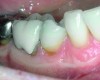

Following active therapy, probing depths of 4 mm or less (Figure 1 and Figure 2) and the absence of bleeding on probing contribute to improved health and stability. Increasing probing depths should alert the therapist to identify etiology and determine whether active periodontal therapy is warranted. The absence of bleeding on probing is a strong predictor of stability, and although the presence of bleeding does not always result in attachment loss, it remains an important parameter to evaluate.14 Bleeding on probing is also an important parameter for assessing implant health during maintenance. Serino et al15 evaluated 27 patients with 19 dental implants over 5 years. Patients were seen every 6 months and they concluded that bleeding on probing was a good predictor for attachment loss and disease progression around the implants (Figure 3).

Fig 1. A deep pocket of 7 mm prior to active periodontal therapy.

Figure 1

Fig 2. Following periodontal regenerative therapy, the tooth with a 3-mm probing depth, which facilitates maintenance.

Figure 2